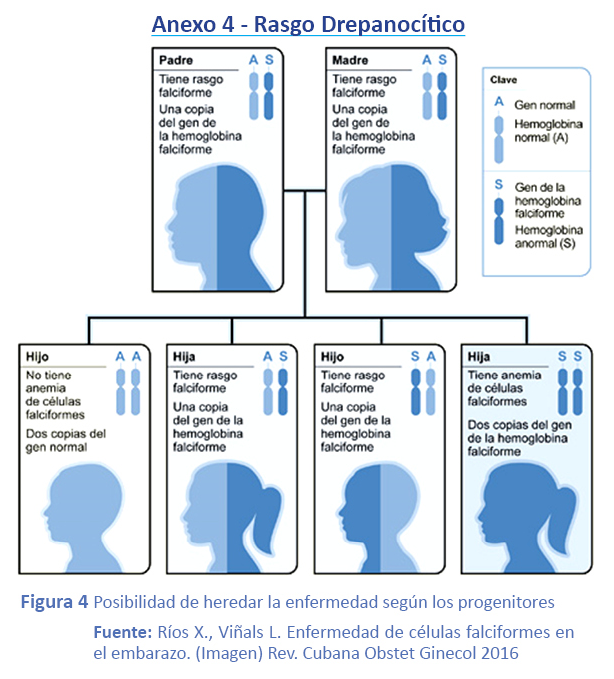

Es una enfermedad con patrones de herencia autosómico recesivo, la cual se encuentra ampliamente distribuida en el mundo; es originada por una mutación puntual en el codón6 de la cadena beta de la hemoglobina, donde la base adenina es cambiada por la valina (GAG: ácido glutámico por GTG: valina); esta modificación estructural da origen a la hemoglobina S(HbS), caracterizada por la presencia de una zona hidrófoba en la superficie de la molécula, que conduce a la formación de fibras largas en la desoxihemoglobina. Esto hace que los glóbulos rojos adquieran forma de hoz y pierdan flexibilidad, provocando con ello vaso-oclusión y bloqueo del flujo sanguíneo produciendo alteraciones en diversos organismos del cuerpo humano23,24. Las personas que heredan un solo alelo para HbS se les denominan portadoras del rasgo drepanocítico o portadores sanos y el fenotipo se expresa como hemoglobina As (Hb AS). Generalmente son asintomáticos y la exploración física es negativa, pasando desapercibidos, por lo que pueden trasmitir el alelo mutado de generación a generación. Afecta aproximadamente a 250 personas en todo el mundo, la mayor incidencia aparece en el continente africano, donde es probable su origen25. La presencia del polímero (HbS) aumenta la viscosidad de la sangre y reduce la deformidad. La enfermedad prolongada y repetida en los glóbulos rojos dañan gradualmente sus membranas, provoca la liberación de agua y iones de (K+ y Cl-) a través de la vía de gardos, provocando la destrucción celular, aumenta la concentración intracelular de Hb y reduce el tiempo para la formación de polímeros de HbS26.

Rasgo Drepanocítico

Son portadores asintomáticos de (HbS) con niveles de Hb, morfología sanguínea y desarrollo físico normales. Las concentraciones de (HbS) son inferiores al 50%, pero pueden tener complicaciones en determinadas condiciones de anoxia. Los heterocigotos Hb (AS) son levemente anémicos y tienen los mismos efectos biológicos que los homocigotos de Hb (AA) en condiciones normales.

8. Diagnóstico neonatal

En revisión de la literatura existe una relación entre rasgo drepanocítico y enfermedad de Legg Calve-Perthes, por sus lesiones óseas y articulares, las cuales evolucionan de manera lenta a partir de un infarto recurrente de la esponjosa a la isquemia, lo cual conllevara a la destrucción ósea y osteoarticular crónica y progresiva de la epífisis femoral, con los signos clínicos y radiológicos de la enfermedad de Legg-Calve-Perthes; de allí la importancia de un diagnóstico neonatal del rasgo drepanocítico a través de la muestra de sangre, la cual obtenemos por punción capilar en el talón para posteriormente realizar el examen de Electroforesis y Cromatografía. También es importante realizar la valoración genética a los familiares.